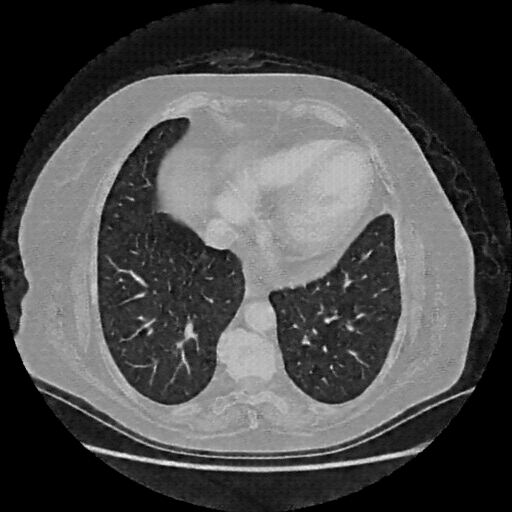

Original NATIVE CT scan (input)

Full window (WL 1023.5, WW 4095 β†’ Low βˆ’1024, High +3071)

Lung window (WL -600, WW 1500 β†’ Low βˆ’1350, High +150)